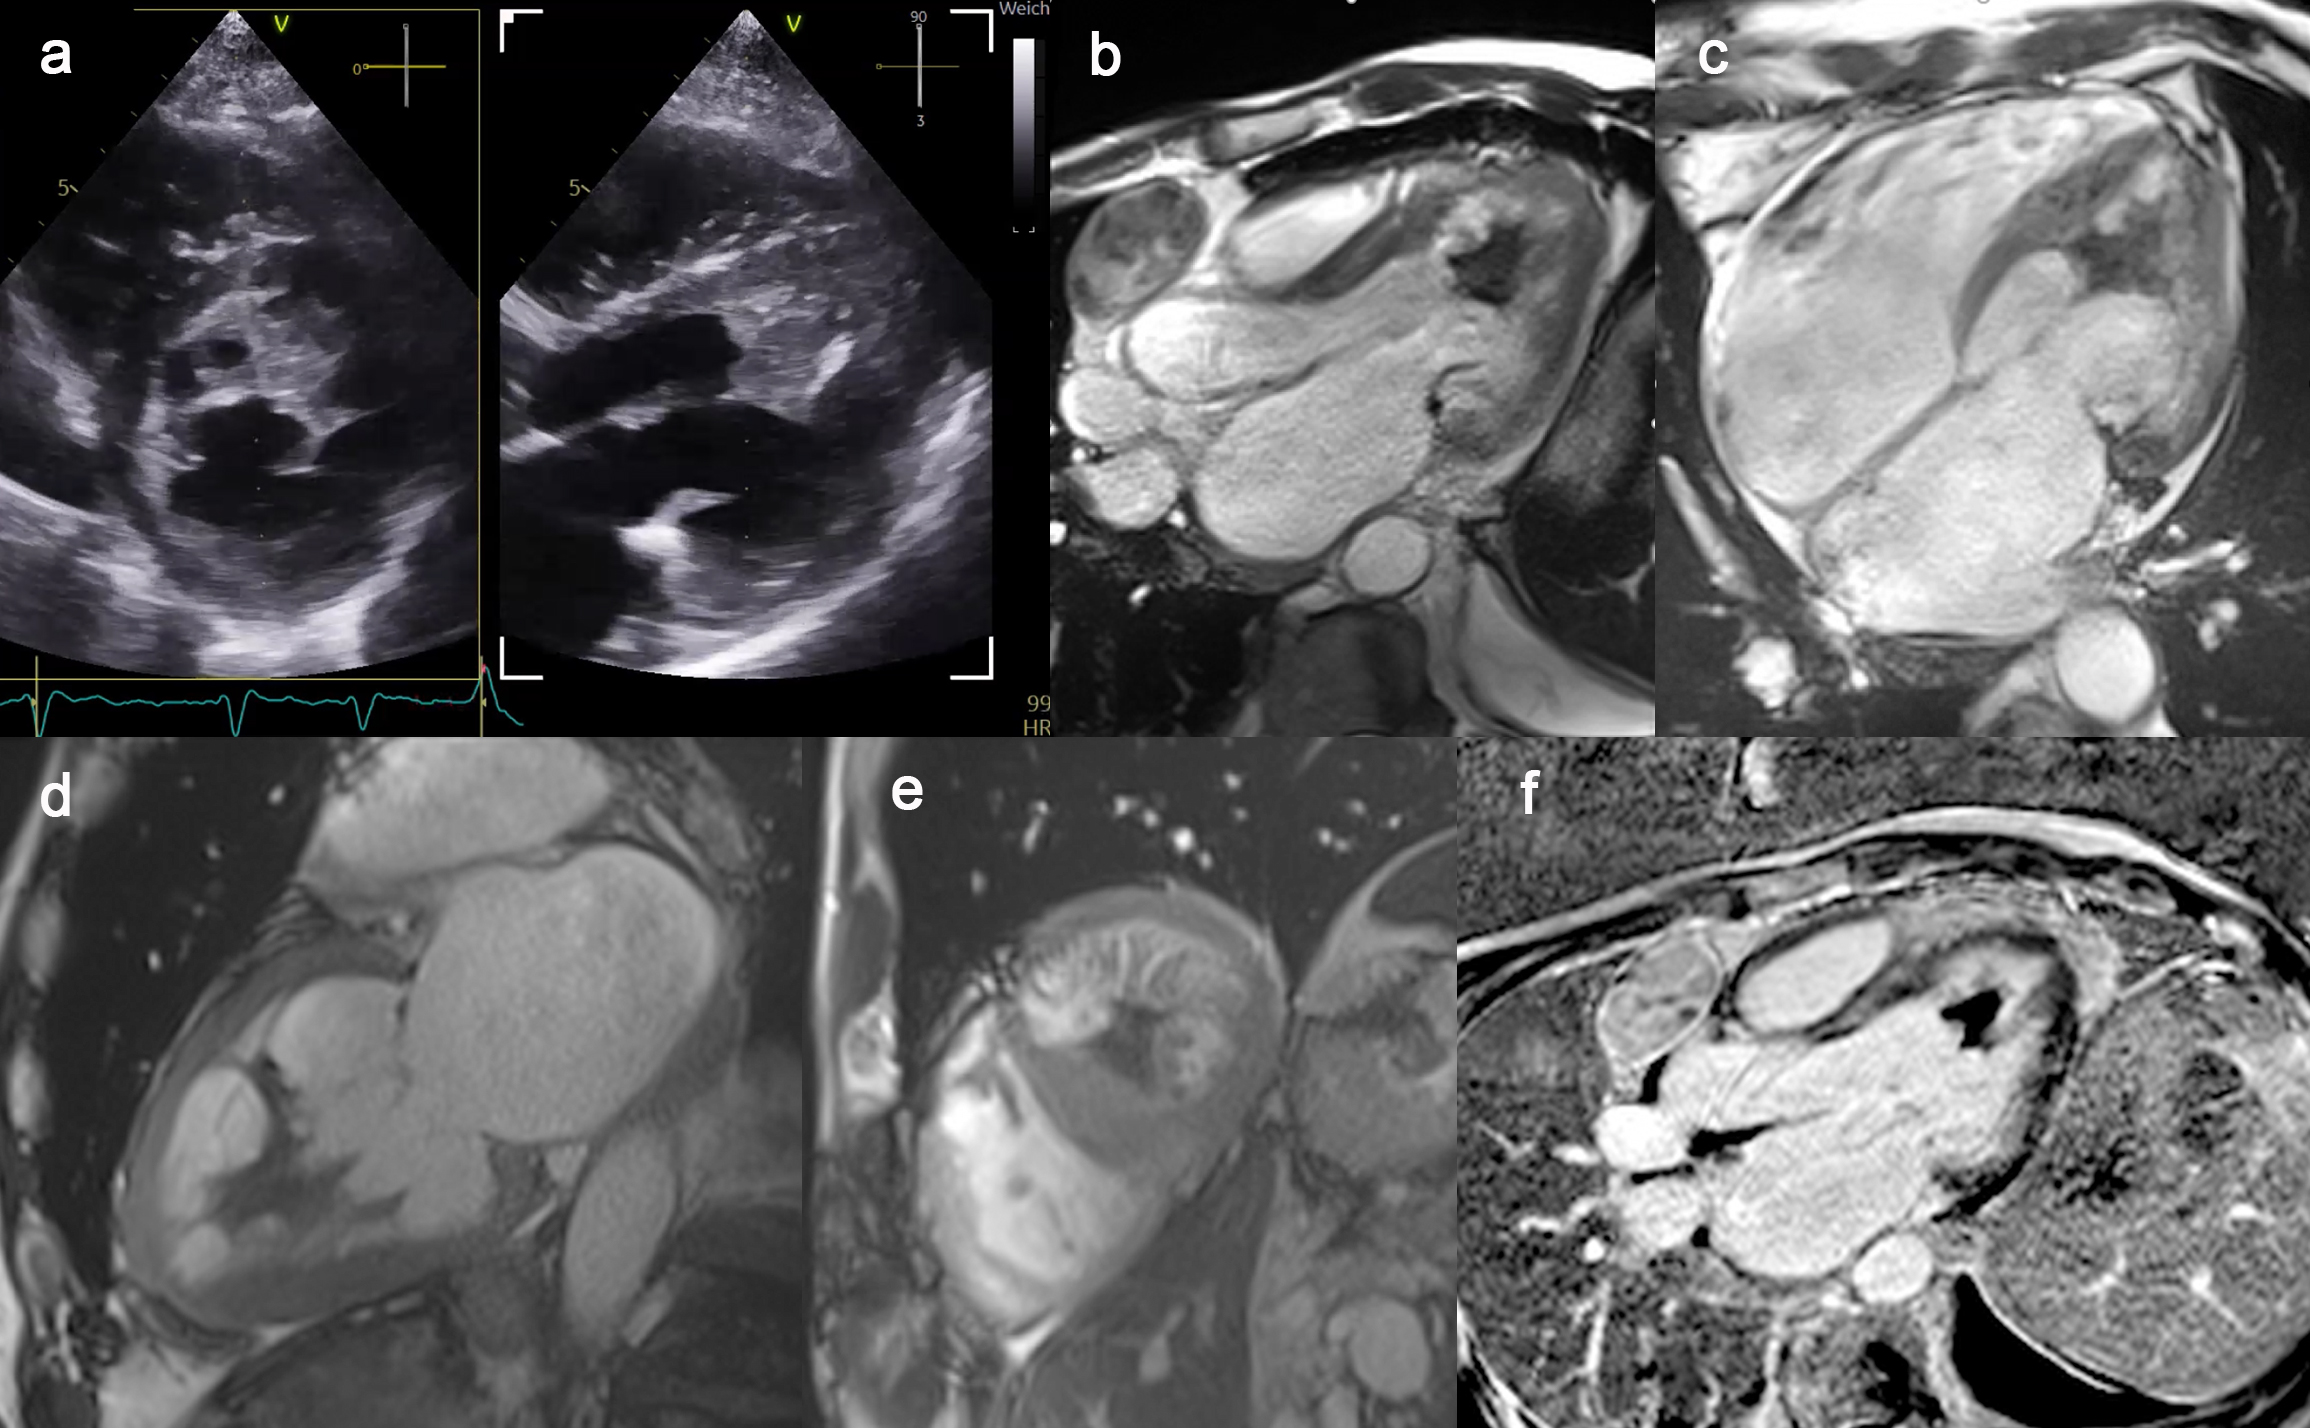

Cardiac Diagnostics:Echocardiography showes a mildly enlarged left ventricle with severely reduced systolic function. A mobile, wall-adherent structure was identified in the apical and midventricular region of the left ventricle, resembling a “Batman signal” (Fig. 1a).

Cardiac magnetic resonance imaging (MRI) confirmed a severely reduced left ventricular ejection fraction of 30% with an end-diastolic diameter of 69 mm and an end-diastolic volume index of 96 mL/m² (Fig. 1b, 1d). The right ventricle showed an end-diastolic volume index of 120 mL/m² (upper limit of normal) and an ejection fraction of 42% (Fig. 1c). No myocardial edema was present. The apical structure in the left ventricle demonstrated no contrast enhancement, consistent with a thrombus. Late gadolinium enhancement revealed patchy intramural fibrosis in the basal and septal ventricular segments (Fig. 1f). Increased trabeculation of the left ventricle suggested a non-dilated left ventricular cardiomyopathy. Thickening of the basal posterior mitral leaflet (Fig. 1b) was consistent with non-bacterial thrombotic endocarditis. The “Batman signal” structure likely represented a thrombus arising from the trabeculated myocardium.

Figure 1: Echocardiography and magnetic resonance imaging of a non-dilated cardiomyopathy, non-bacterial thrombotic endocarditis and a left ventricular thrombus appearing as a “Batman signal” in the left ventricle